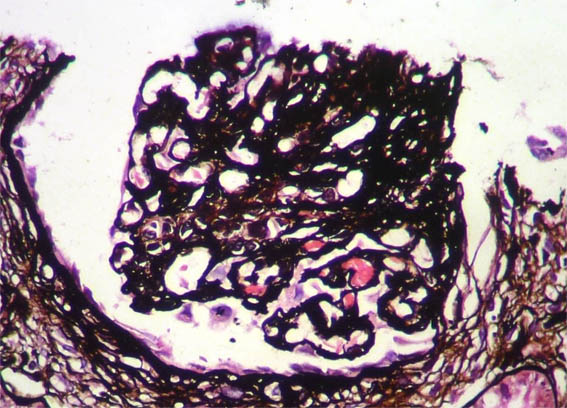

Figure 7. Masson's

trichrome stain, X400.